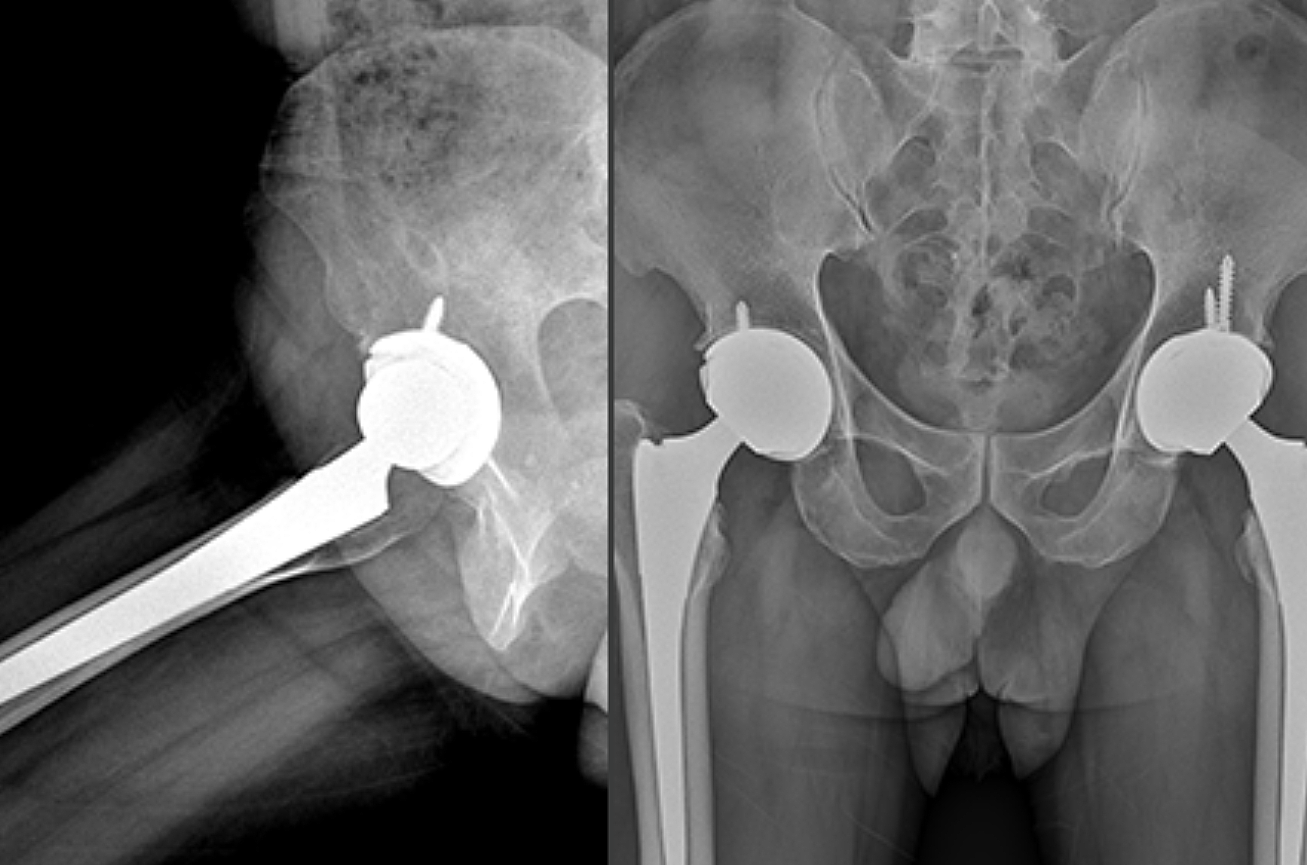

고관절은 골반 뼈 속에 공처럼 생긴 대퇴골의 골두가 맞물린 관절입니다. 대퇴골두는 다른 부위에 비해 혈액 순환 장애가 쉽게 올 수 있으며, 혈액 순환 장애는 대퇴골두 무혈성 괴사를 유발합니다. 뼈가 썩으면 몸의 하중을 정상적으로 견디지 못해 미세구조에 골절이 생기고, 심각한 통증이 발생합니다.

고관절 통증 증상은 조기에 발견하고 치료받는 것이 무엇보다 중요합니다. 고관절 손상이 심하지 않고 통증이 가볍다면 약물치료와 운동치료 등 보존적 치료를 통해 회복할 수 있습니다. 하지만 고관절 손상이 심하고 일상생활에 지장을 줄 만큼의 심한 고관절 통증 증상이 있는 경우라면 괴사된 관절을 제거하고 인공관절을 삽입하는 고관절의 인공관절 치환술을 해야 합니다.